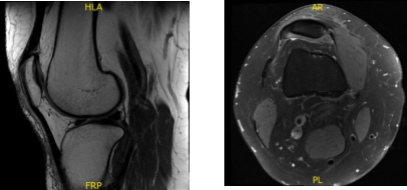

X-ray and MRI were presented in the office. Found vertical tear at the free edge margin of the posterior horn medial meniscus, with mild undersurface/free edge fraying of the body segment. Mild medial femorotibial compartment chondral loss. Mild patellofemoral compartment chondral wear, preferentially over the medial aspect of the compartment.

Lateral patellar tilt with mild lateral positioning of the patella. These findings may be seen in the setting of patellar malt racking. Features which may be seen in the setting of iliotibial band friction syndrome.